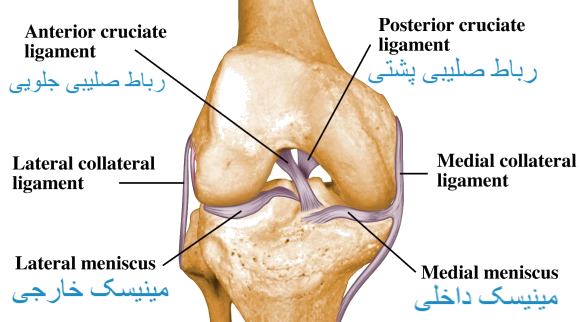

مفصل زانو بزرگترین مفصل بدن است و برای فعالیت هایی مانند راه رفتن، دویدن، پریدن و ایستادن بسیار مهم است. این مفصل پیچیده ای است که از استخوان ها، رباط ها، تاندون ها و غضروف تشکیل شده است که همه با هم کار میکنند تا ثبات و انعطاف پذیری را فراهم کنند. مفصل زانو امکان انجام حرکاتی مانند خم شدن، باز شدن و چرخش را فراهم می کند و آن را برای وظایف و فعالیت های روزمره ضروری می کند. با این حال، همچنین مستعد آسیب و شرایطی مانند آرتروز است. مراقبت از زانو از طریق ورزش زانو، قرارگیری مناسب و استراتژی های پیشگیری از آسیب مهم و حیاتی هست.

ساختار مفصل زانو :

– غضروف مفصلی : انت های استخوان ران، درشت نی و کشکک را برای کاهش اصطکاک و جذب ضربه می پوشاند.

– مینیسک : دو تکه غضروف C و O شکل که به عنوان ضربه گیر عمل می کنند و به تثبیت مفصل زانو کمک می کنند.

– رباط ها : ایجاد ثبات و نگه داشتن استخوان های مفصل زانو از جمله رباط صلیبی جلویی (ACL)، رباط صلیبی پشتی (PCL)، رباط جانبی داخلی (MCL) و رباط جانبی خارجی (LCL).

– غشای سینوویال : کپسول مفصل را می پوشاند و مایع سینوویال ترشح می کند که مفصل را روان کرده و اصطکاک را کاهش می دهد.

– بورس : کیسه های پر از مایع که به کاهش اصطکاک بین تاندون ها و استخوان ها کمک می کند.

عضلات و تاندون ها

– تاندون کشکک : کشکک را به استخوان درشت نی متصل می کند و به باز شدن زانو کمک می کند.

– عضلات چ هار سر ران : گروهی متشکل از چ هار ماهیچه در جلوی ران که با هم کار می کنند تا زانو را صاف کنند.

– عضلات همسترینگ : گروهی از عضلات پشت ران که به خم شدن زانو کمک می کنند.

– آسیب به زانو، مانند پارگی رباط یا منیسک